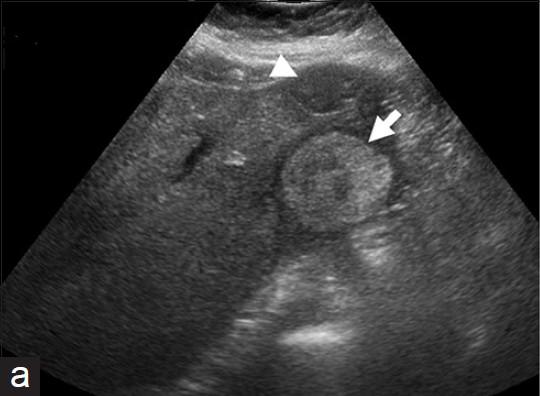

What is the sonographic appearance of Hepatic candidiasis?

Multiple

small

bull’s-eyes or target

lesions

Hypoechoic mass

echogenic core